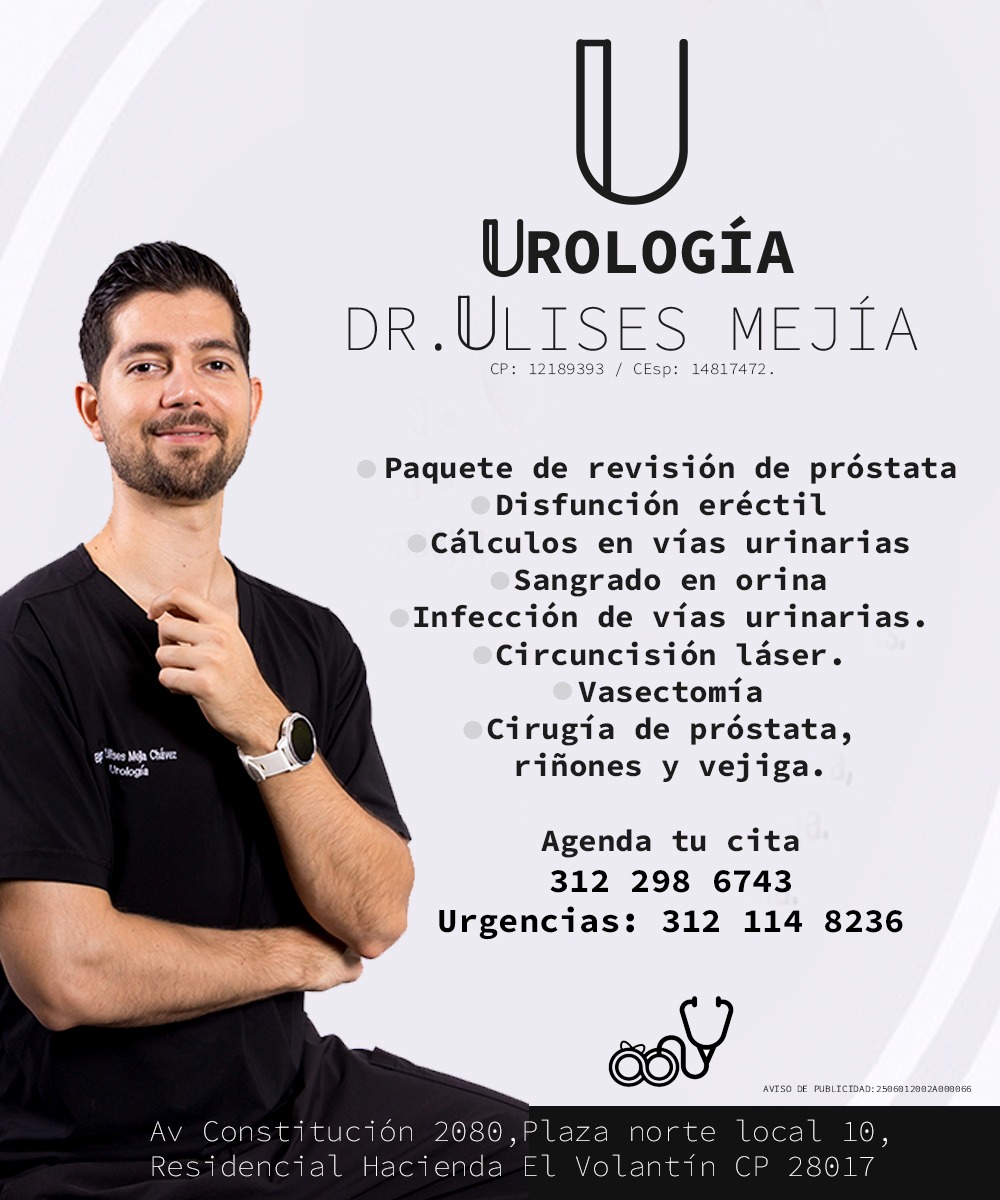

El Dr. Ulises Mejía es un urólogo destacado en Colima, reconocido por su profesionalismo y atención personalizada. Ubicado en Av. Constitución 2080, Puerta del Sol, ofrece servicios especializados en salud urológica para pacientes que buscan un cuidado integral y de calidad. Con una calificación de 5 estrellas basada en 10 opiniones, sus pacientes destacan su capacidad, inteligencia y dedicación en cada consulta y procedimiento. El Dr. Mejía se caracteriza por brindar un trato cercano y atento, asegurando que cada paciente reciba un diagnóstico preciso y un tratamiento efectivo. Sus servicios incluyen diagnóstico y manejo de enfermedades urológicas, cirugías y seguimiento postoperatorio, siempre con un enfoque humanizado. Para agendar una cita o solicitar información, puede contactarse al teléfono 312 114 8230 o visitar su perfil profesional en Instagram. Si busca un especialista confiable y con amplia experiencia en Colima, el Dr. Ulises Mejía es una opción recomendada para el cuidado de su salud urológica.

Dr. Ulises Mejía is a highly regarded urologist based in Colima, known for his professionalism and personalized care. Located at Av. Constitución 2080, Puerta del Sol, he provides specialized urological health services to patients seeking comprehensive and quality care. With a perfect 5-star rating from 10 reviews, patients highlight his expertise, intelligence, and dedication during every consultation and procedure. Dr. Mejía is recognized for his attentive and compassionate approach, ensuring accurate diagnoses and effective treatments. His services include diagnosis and management of urological conditions, surgeries, and postoperative follow-up, all delivered with a patient-centered focus. To schedule an appointment or request more information, contact him at 312 114 8230 or visit his professional Instagram profile. For those looking for a reliable and experienced urologist in Colima, Dr. Ulises Mejía is a highly recommended choice for urological health care.

📞 312 114 8230 🌐 https://www.instagram.com/drmejia_urologo?igsh=ZmF4bjBlcW04Y2l1